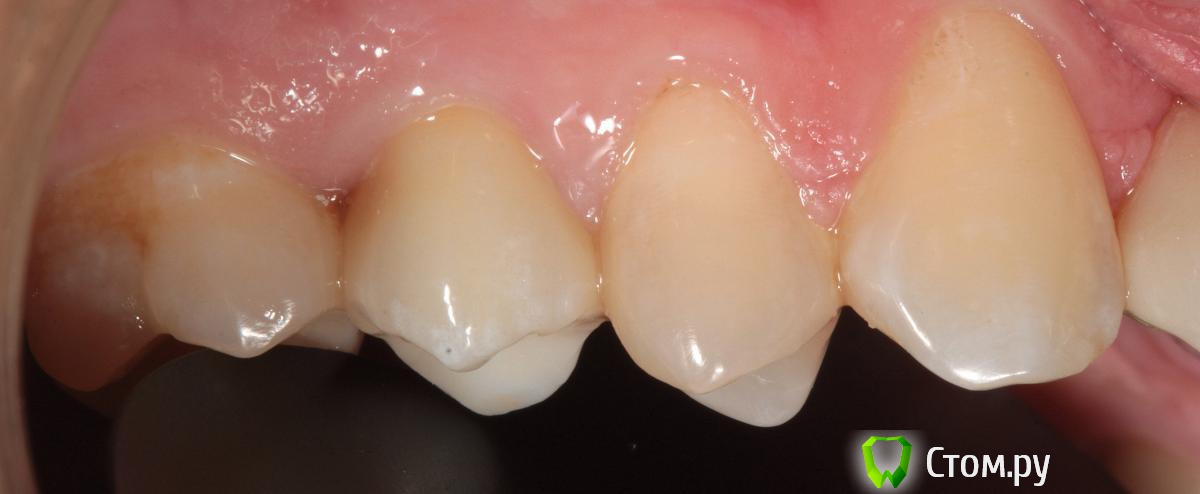

SDC Опубликовано 19 ноября, 2014 Поделиться Опубликовано 19 ноября, 2014 (изменено) Prettau, извините, не знаю, как редактировать название темы. Здравствуйте всем. В хирургическом много практиков, а по протетике - много теории)). Итак, разбавляю вино. (теория вечна)Протезирование премоляров коронками Преттау с нанесением керамики вестибулярно.Много фото, прошу прощения, поэтому без радикала, превью. Наверное даже так лучше, потому, что по клику откроются не сжатые фото, а радикал жмет.Протезирование в течение 2 недель. Фиксация на фуджи, без коффердама, но в сухих условиях (коффер не поставить по причине глубокий дистальной границы препарирования на обоих премолярах - глубокий кариес проксимальных поверхностей в анамнезе)Рг-контроль на предмет остатков цемента и на последнем фото удаленные излишки цемента на перчатке. Изменено 19 ноября, 2014 пользователем SDC 7 Ссылка на комментарий

RuStom Опубликовано 19 ноября, 2014 Поделиться Опубликовано 19 ноября, 2014 Красиво. не отличить от настоящего. Сколько техничка выходит, можно в личку Ссылка на комментарий

SDC Опубликовано 20 ноября, 2014 Автор Поделиться Опубликовано 20 ноября, 2014 Хорошая работа! Единственно на 26 я бы пломбу поменял заранее, чтобы в будущем контакт не нарушать. Фуджи One или Plus? Разве первый требует изоляции коффером?Наверно, на 16? Она ~ 1 год назад сделана, перед фиксацией была полировка пломб на контактных поверхностях соседей. Фуджи 1, Обеспечение хорошей изоляции, необходимо для любого цемента, в данном случае несколько нитей ультрапак в проблемных местах. Ссылка на комментарий

SDC Опубликовано 20 ноября, 2014 Автор Поделиться Опубликовано 20 ноября, 2014 Отличный результат. Позвольте несколько вопросов.СВШ в боковых не ставите вообще,если да,то по какой причине?Как думаете антагонисты не будут истираться?Вы как-то меняете анатомию контакта при глубоких дефектах и недостатка сосочка?Спасибо.Спасибо Роман.По поводу штифтов. На самом деле, не имеет значения для меня.Важно, что не было титановых во фронтальном отделе (открываются при редукции тв.тк. небольшой объем композита вокруг штифта, что приводит к хрупкости билдапа и иногда металл.штифты светят через композит и керамику)Антагонисты истираться будут, а цирконий - нет. Что поделаешь.Сейчас мы с техником делаем нанесение вестибулярно и по скатам бугров, для уменьшения негативного эффекта повышенной прочности циркония и ускорения сдаваемости.контакт всегда площадочный, пятно контакта в корональной 1/4.Дефицит мягких тканей керамикой никогда не восполняем. Моделировка коронки максимально анатомична. Ссылка на комментарий